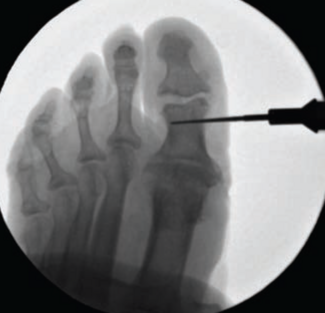

Duane J. Ehredt, Jr.; Matthew M. Reiner; Brennan K. Reardon, DPM; Lauren Lindsay Schnack, DPM, MS, AACFAS, FACPM, DABPM

This case series reports on the outcomes of a minimally invasive technique for offloading of the hallux in 5 patients with recalcitrant hallux ulcerations.